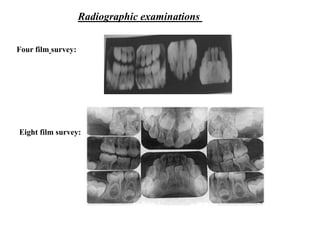

Radiographic examinations

Twelve film survey:

Sixteen film survey:

Four film

survey:

series consists of

a maxillary and

mandibular

occlusal

radiographs and

two posterior

bitewing

radiographs.

Eight film survey:

• This survey includes a

maxillary and

mandibular anterior

occlusal radiographs.

• Four molar periapical

• Two posterior

bitewings

• This survey include

mandibular permanent

incisor periapical

• Four primary canine

periapical

bitewing radiographs

Sixteen film survey: This examination consists of the twelve-film

survey and the addition of four permanent molar radiographs.